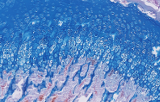

Soda-lime glass remains the most widely used material due to its cost-effectiveness and hydrolytic resistance. Borosilicate glass provides superior chemical and thermal stability and exhibits lower autofluorescence, making it suitable for fluorescence microscopy. Pre-cleaned and autoclavable slides reduce contamination and ensure low background signals in sensitive applications such as fluorescence microscopy, cytogenetics, or palynology.

- Borosilicate glass:

- higher thermal and chemical durability.

- lower autofluorescence for fluorescence imaging.